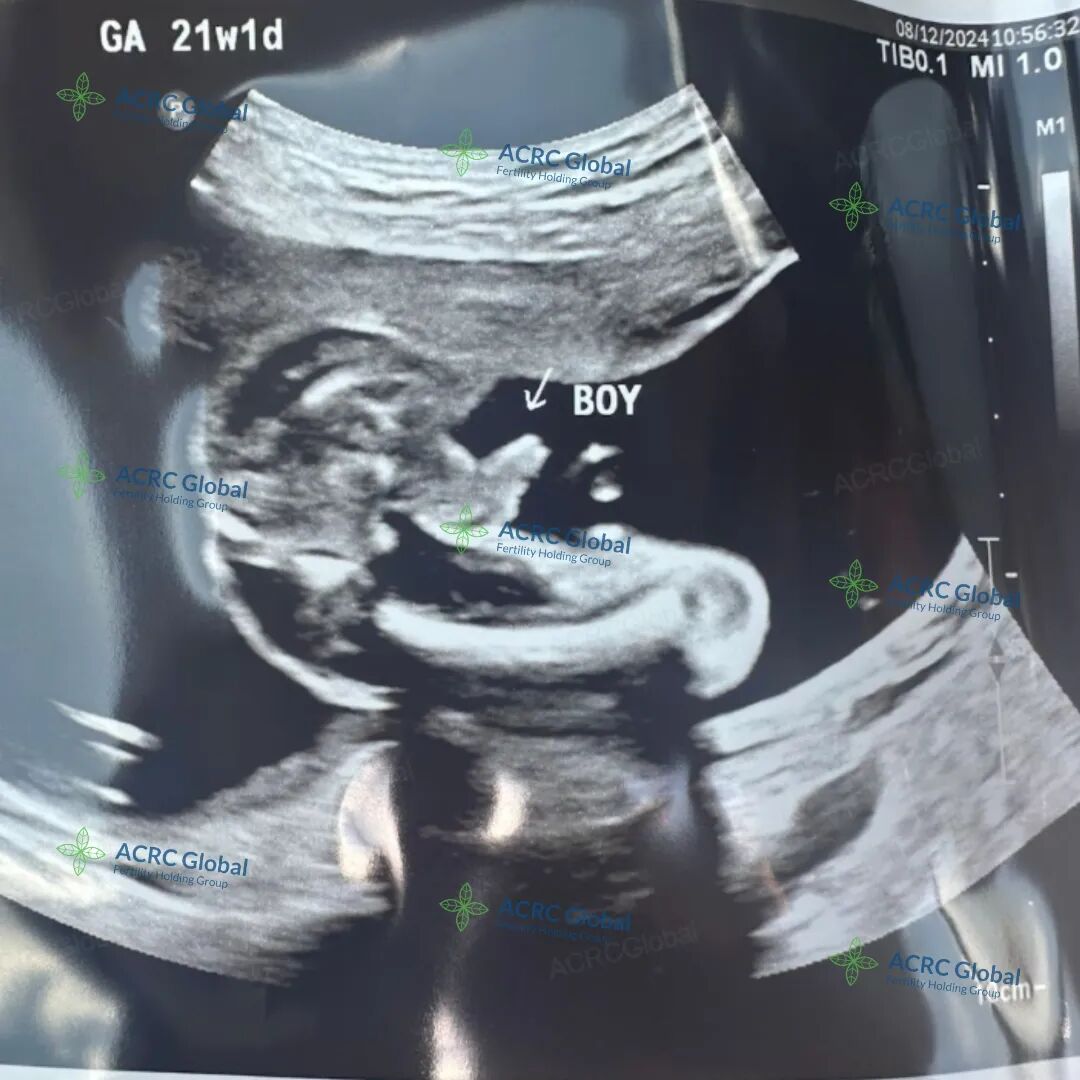

爱妈H也顺利进入了孕中期,目前宝宝已经21周大。宝宝大约27厘米长,重约360克,像一个胡萝卜大小。这个阶段是宝宝稳定的发育期,各项身体功能和感官正在逐步完善。准父母对即将到来的男宝充满了期待!